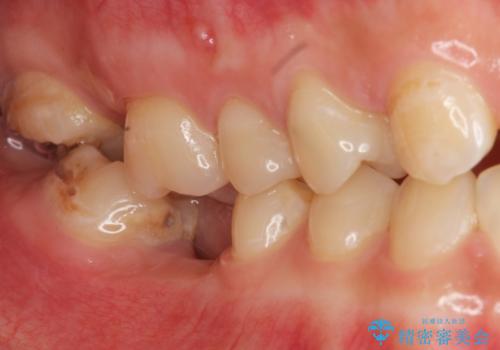

- 上下1本づつの歯を失い、噛めないことの改善を求めて来院されました。

保存可能な歯の虫歯・根管治療を行い、喪失した部分はインプラントを埋入、オールセラミックジルコニアクラウンを製作し審美的に仕上げていきます。

今回下顎の欠損部位はブリッジも検討されましたが、並行性の観点から最後方臼歯の神経を取るリスクを抑えるためインプラント治療を選択しました。